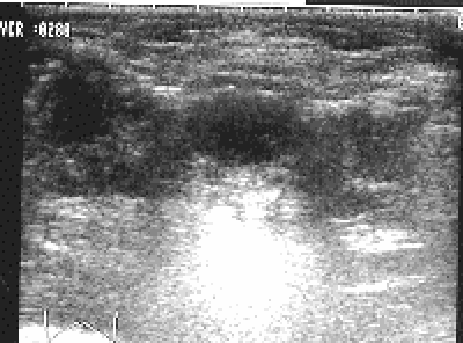

確定診断は超音波断層像によっておこないます。超音波断層像による診断法が登場するまでは、X線診断が確定診断法として最も信頼性が高く、今日でも奇形を伴った脱臼の診断や、1歳以後の脱臼の診断には欠かせない診断法であります。しかし、被爆ということを考えると、乳児検査ではなるべくX線診断は避けるようにしたいものです。超音波診断は害がないばかりか、X線診断よりも正確です。

視診・触診、超音波検査によって脱臼を分類します。私は股関節を曲げた時の大腿骨頭の位置によって脱臼の程度をA, B, C の3つに分類し、脱臼の程度に応じた治療をおこなっております。

タイプA(亜脱臼)とは、股関節を曲げて開いた時に大腿骨と臼蓋とのズレがわずかで、両方の軟骨どうしは常に接触を保っている場合を言います。タイプAの中で、股関節の位置によっては骨頭と臼蓋とのズレがなくなる場合もあり、これをタイプAI(ボーダーライン亜脱臼)と呼びます。さらに、タイプAIのうち、臼蓋の形成が良好な場合をタイプAI-I, 臼蓋の形成が不十分な場合をタイプAI-IIと分類します。タイプAII(亜脱臼)とは股を曲げて開いた状態で大腿骨頭と臼蓋とのズレのなくならないものをとします。

タイプB(完全脱臼)とは大腿骨と臼蓋とのズレが大きくなって、股関節を曲げたときでも両方の軟骨どうしの接触がない場合を言います。

タイプC(完全脱臼)とは高度な脱臼で、股関節を開いた時には脱臼した骨頭の中心が臼蓋縁より下に位置している場合です。